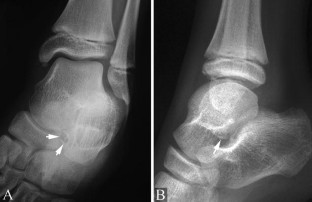

Osteochondritis dissecans of the talus is classically characterized by an abnormality of the articular cartilage of the talar dome. We report a rare case of a lesion of the subtalar facet in a 10-year-old boy. The lesion was responsible for a painful ankle with secondary instability. The diagnosis was made using plain radiographs and CT, which showed a well-circumscribed osteochondral fragment demarcated from the adjacent bone by a radiolucent line. The clinical outcome was favourable after a 6-week period with a non-weight-bearing short-leg cast.

Fig. 2